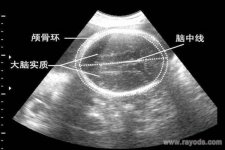

怀儿子双顶径一般都会大吗 怀孕以后,做得最多的就是B超检查了。拿到B超单子后,我们会看到有显示胎儿双顶径的信息,想必很多孕妈妈都遇到过胎儿双顶径偏大的情况。

胎儿双顶径偏大,表明胎儿宝宝头部比较大而已,并不能说明其是男孩或是女孩。医生通过胎儿双顶径来观测宝宝的发育情况,B超检查胎儿双顶径数据,可判断出其是否出现头盆不称的情况,以此来决定是否可以顺产。

胎儿双顶径,又称BPD,通过B超检查数据推断而出。胎头双顶径是一个参考性的数据,医生用它来观察胎儿的发育情况;判断能否有头盆不称;能否顺利分娩的情况。